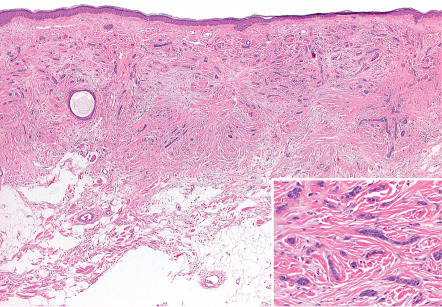

Pathology

Desmoplastic trichoepitheliomas are composed of cords of basaloid cells, often two cells wide, arrayed interstitially amongst coarsened collagen bundles ( Fig. 111.14 ) . The lesions are relatively circumscribed and are often confined to the upper two-thirds of the reticular dermis, although this is difficult to appreciate in biopsies en parte . Small cystic foci of isthmic or infundibular keratinization may be present, and if these cystic spaces are predominant, the designation trichoadenoma is apt. The cornifying cysts can rupture and elicit a granulomatous reaction, and small secondary foci of calcification may also be identified .